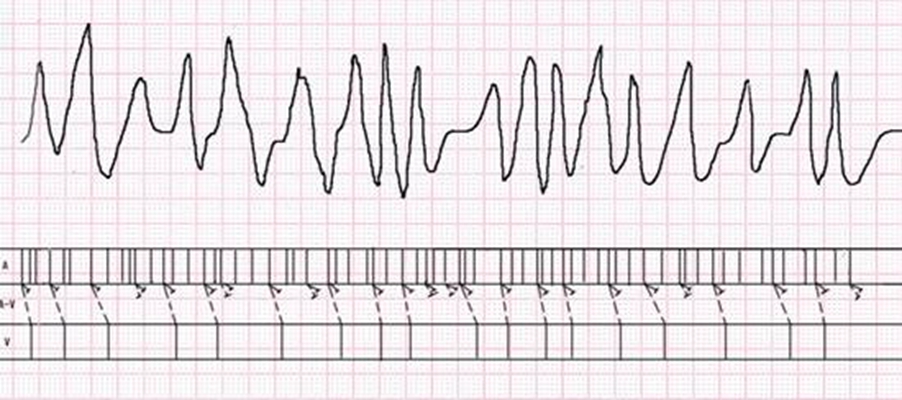

預激綜合症圖片

預激綜合徵心電圖 (82)

預激綜合徵心電圖 (83)

預激綜合徵心電圖 (84)

預激綜合徵心電圖 (85)

預激綜合徵心電圖 (86)

預激綜合徵心電圖 (87)

預激綜合徵心電圖 (88)

預激綜合徵心電圖 (89)

A:預激綜合徵合併房速的時候,心電圖可以出現快速而且寬大畸形的QRS波群,有點類似於室性心動過速,典型的預激波有可能會被覆蓋。合併房速的時候會有極快速的心室率、QRS波群會寬大畸形,也有可能比較易變和複雜。患有預激綜合症合併房速,如果有明顯的心……